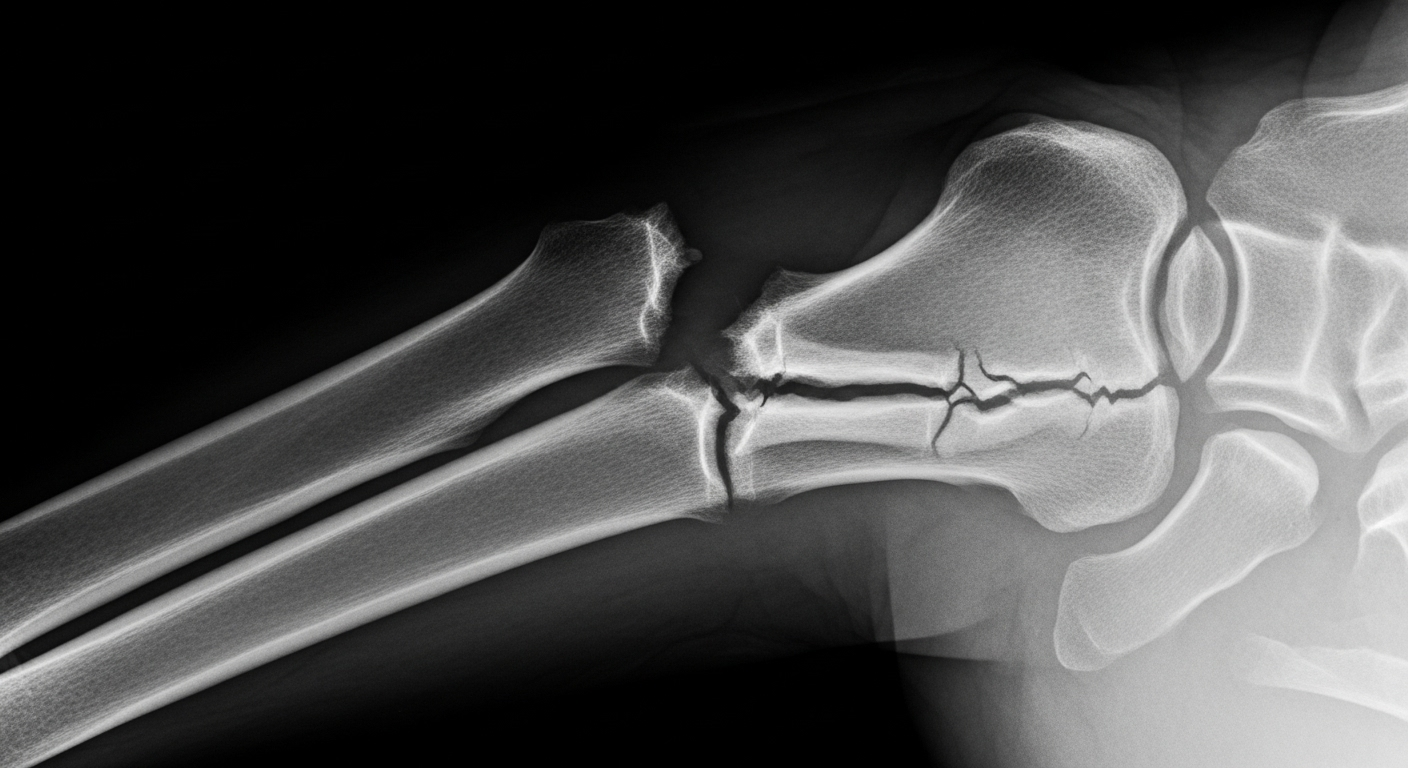

Face à ces théories, le Dr Suhail Hussain, un médecin généraliste, apporte un éclairage bien plus terre-à-terre. Il explique que la probabilité de se casser un os n’est « pas du tout due au hasard ou à une protection divine ». Selon lui, c’est en réalité un mélange de plusieurs facteurs bien concrets : « un mélange de vos gènes, de votre mode de vie, et même de ce que vous mangez, qui pourrait rendre vos os plus faibles ou plus forts ».

Le premier élément clé, c’est notre héritage génétique. « La solidité des os est en grande partie héréditaire », explique le Dr Hussain. Cela inclut la densité de nos os, la manière dont notre corps utilise le calcium, et même la structure générale de notre squelette. Certains d’entre nous sont tout simplement nés avec des os naturellement plus denses et plus solides. D’autres, au contraire, ont des os plus fins qui peuvent se casser plus facilement sous la pression.